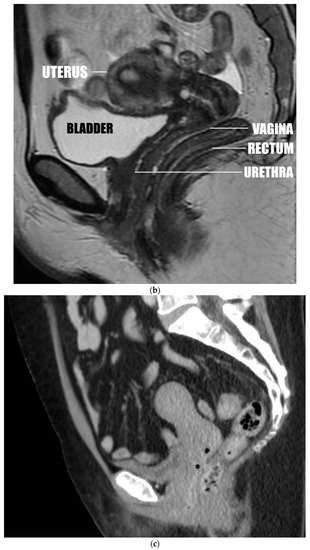

Figure 1.

(a) Anteverted uterus with the fundus near the pubic body. (b) Anteverted uterus in the most common position, close to perpendicular. (c) Anteverted uterus, above perpendicular, separated from the bladder. (d) Mildly retroverted uterus inserting at the apex of the vagina. (e) Markedly retroverted uterus inserting on the posterior wall of the vagina. Sample lines were drawn, and a sample measurement was placed on this image. The double layered line was drawn from the introitus of the vagina to the center of the surface of the cervix. The single layered line was drawn from this point parallel to the axis of the cervix.

One reader (A.A.) observed and recorded changes in the anatomic relations of the uterus to surrounding structures as the angle of version (from mild anteversion to marked retroversion) and insertion site (anterior, apical, posterior) changed, as displayed by CT and MRI. This primarily involved changes in the position of the uterus relative to the urinary bladder, vagina, and rectum (Figure 1a–e).

Observations of CT and MRI images showed that in 236 of 261 cases of anteriorly inserted anteversion, the uterine fundus was superior to and contiguous with the urinary bladder, which is supported by the urethra and the pubic body. The cervix was superior to and contiguous with the vaginal walls and the rectosigmoid colon, which is supported by the pelvic floor (Figure 1a,b).

In the remaining 25 cases of anteriorly inserted anteversion the uterine fundus was superior to and separated from the bladder, but the cervix remained immediately superior to the vaginal walls and rectosigmoid colon (Figure 1c). One uterus considered apically anteverted by measurement had the same anatomic relations.

The remaining 12 apically inserted anteverted uteri were positioned vertically, posterosuperior to the urinary bladder at a shallow angle and anterior to the rectosigmoid. The cervix was surrounded by the vaginal walls and the vaginal lumen was below the cervix. In all 44 cases of apical retroversion, the cervix was positioned vertically, posterior to the bladder and anterosuperior to the rectosigmoid at a shallow angle. The cervix was surrounded by the vaginal walls (Figure 1d). In four of these cases, the uterine fundus was contiguous with the presacral soft tissues or lower lumbar spine. In five of these cases, the uterine fundus was superior to and contiguous with the bladder when the uterus was enlarged and anteflexed.

All five posteriorly inserted retroverted uteri were superior to and contiguous with the rectosigmoid colon, which was supported by the pelvic floor and coccyx (Figure 1e).

In this study, we found that the uterus can be located along an arc extending from the pubic bone and urinary bladder to the coccyx and rectum (Figure 1a–e). Of the retroverted uteri, 89.8% were located along an arc of less than 40 degrees past the plane of the vagina before rotation was limited by the rectosigmoid colon, the lower lumbar spine, or the sacrum (Figure 1d), and 10.2% of retroverted uteri rotated further and inserted in the posterior wall of the vagina (Figure 1e). Hence, our study demonstrates that most retroversion is mild with resultant insertion of the cervix into the vaginal apex. This results in alignment of the axis of the cervix with the axis of the vagina.

We found that most anteverted uteri (95.3%) (Figure 1a–c) inserted in the anterior wall of the vagina centered on a peak of 60 to 100 degrees. A much smaller proportion of anteverted uteri (4.7%) than retroverted uteri inserted at the vaginal apex. Hence, a much smaller proportion of anteverted uteri would be subject to the postulated mechanisms leading to uterine prolapse.

Observations of images from this study appear to show that most anteriorly inserted anteverted uteri receive support from the urinary bladder, the bodies of the pubic bones, the anterior and posterior walls of the vagina, the rectosigmoid colon, and the pelvic floor (Figure 1a). The only structures below apically inserted uteri are the vaginal lumen and the urinary bladder or rectosigmoid colon at shallow oblique angles (Figure 1c). This suggests that there is less support from surrounding organs for apically inserted uteri, providing an additional possible explanation for the greater incidence of uterine prolapse in uterine retroversion.